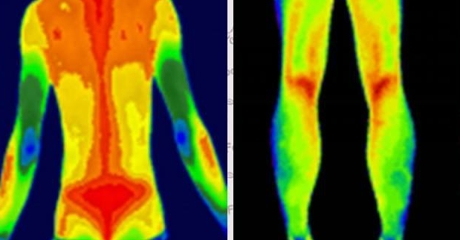

自動(dòng)標(biāo)注肢體溫差>1℃的區(qū)域(提示血栓風(fēng)險(xiǎn))

動(dòng)態(tài)監(jiān)測(cè)糖尿病足微循環(huán)變化

案例:北京某三甲醫(yī)院用其提前7天預(yù)警糖尿病患者足部壞死風(fēng)險(xiǎn)

炎癥可視化

智能識(shí)別類風(fēng)濕關(guān)節(jié)炎的“梭形熱區(qū)”

量化評(píng)估強(qiáng)直性脊柱炎進(jìn)展程度

(插入示意圖:脊柱炎癥熱圖 – 紅色熱區(qū)與MRI病灶位置完全吻合)

乳腺癌:患側(cè)乳頭溫度升高0.5-2℃

甲狀腺癌:腫瘤區(qū)域呈現(xiàn)“熱島效應(yīng)”